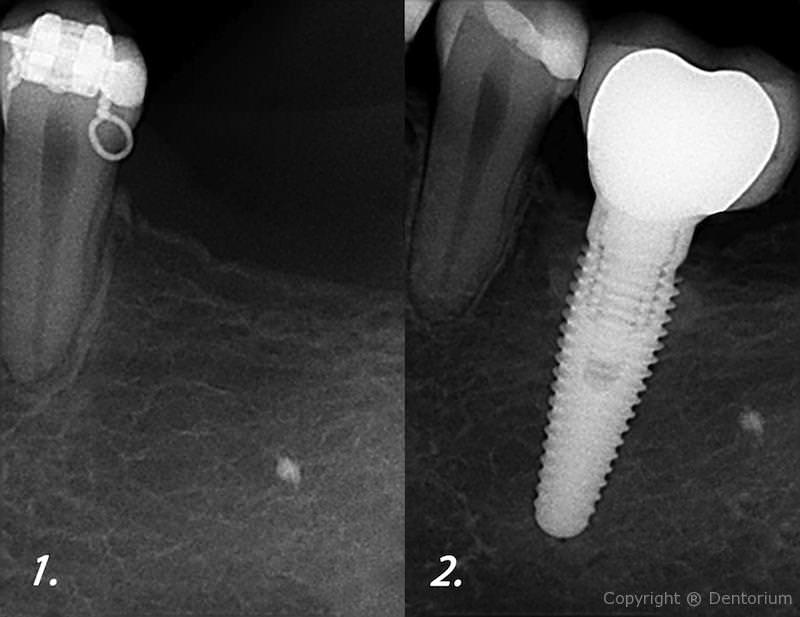

L’Impianto dentale sostituisce il dente mancante totalmente riabilitando la funzione e l’estetica della bocca.